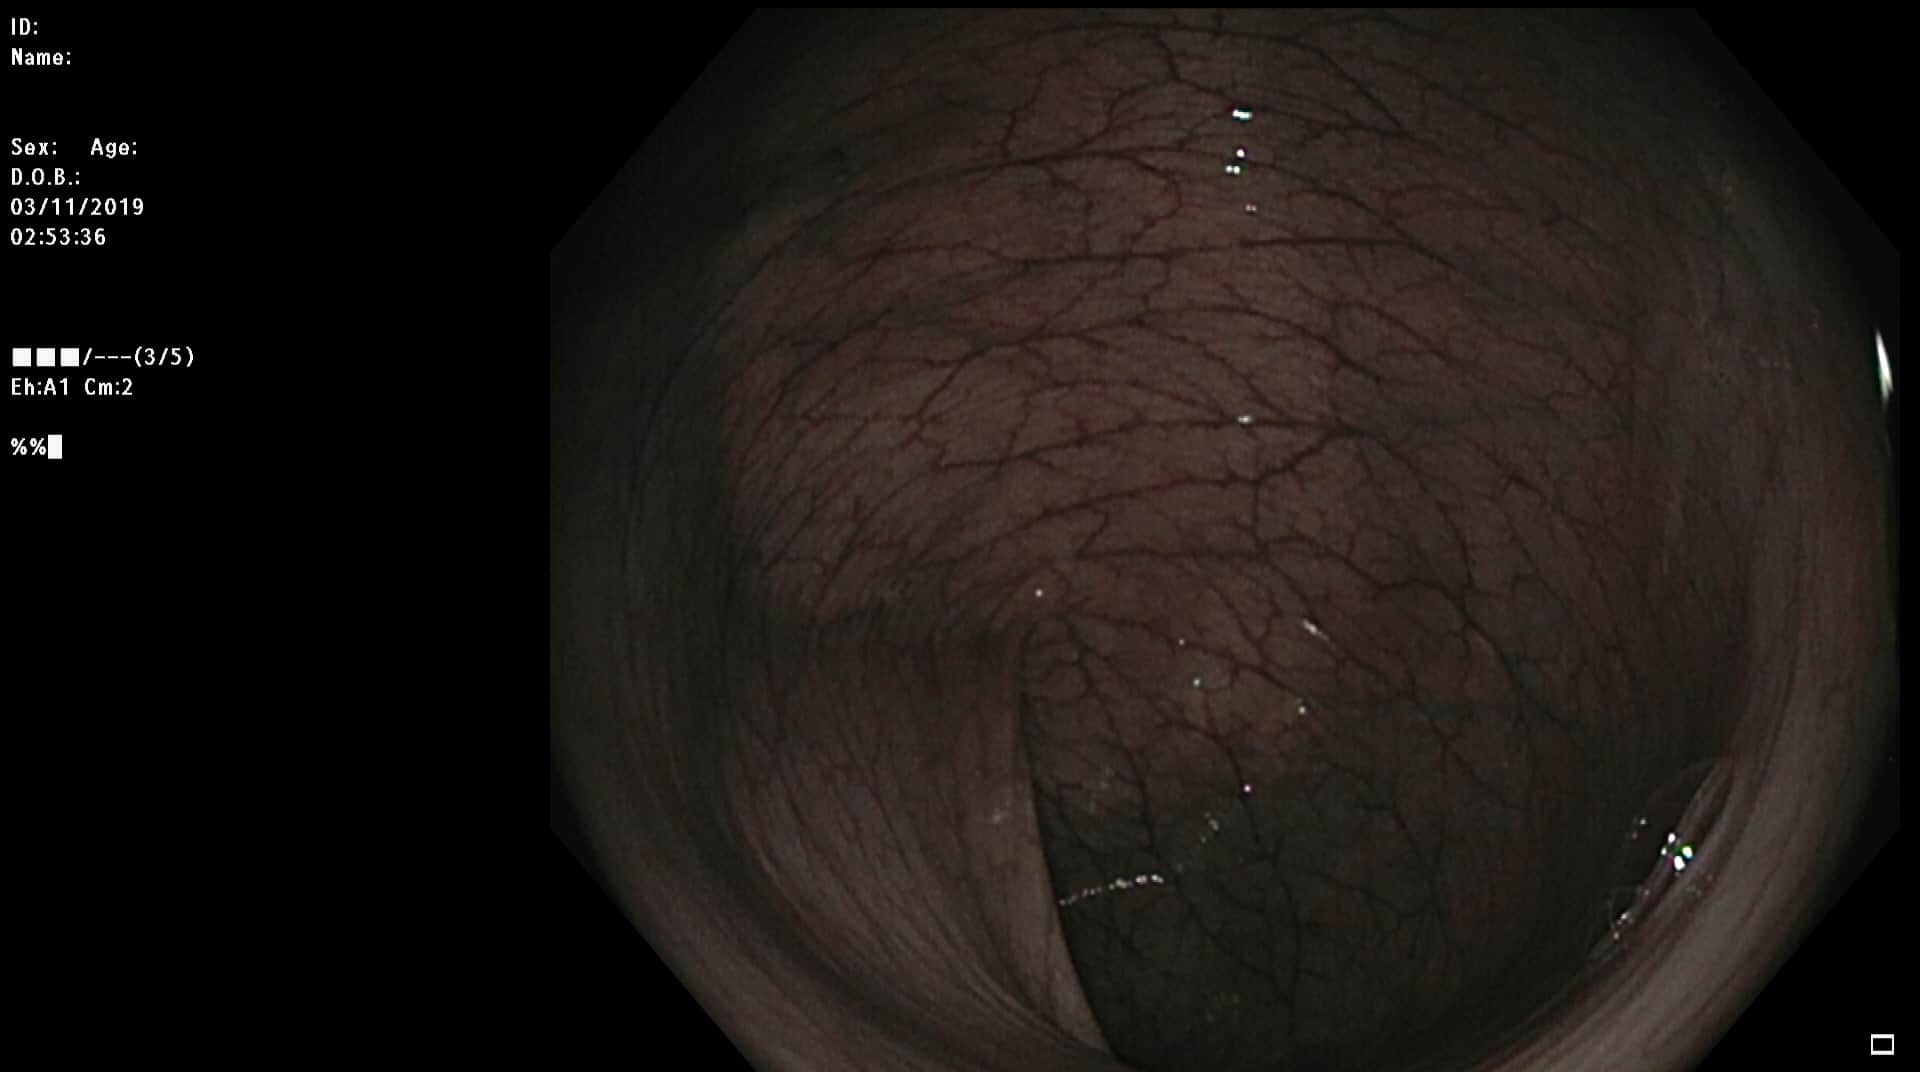

Tidligere frisk mann f.-33 som kom til koloskopi pakkeforløp pga magesmerter, endret avføring, Hb-fall tre enheter og pos hemofec. Trombocytopeni. Bedring etter oppstart PPI. Dag 1 dårlig tømt, kun distal skopi, men funn av stor polypp i venstre colon. Ved gastroskopi ulcerasjoner i tilheling. Dag 2 koloskopi med funn av atypiske polypøse lesjoner i mye av colon, både store og små. Bilde nr. 2 og 3: analt og oralt for sigmoideumvolvulus. Diagnose?